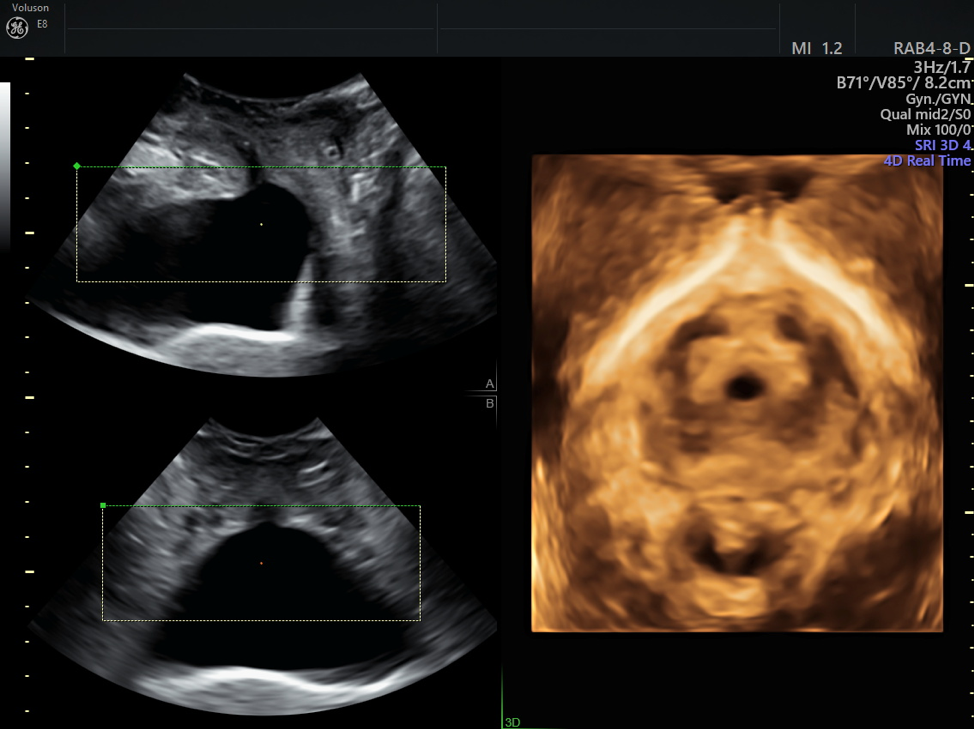

From www.volusonclub.net